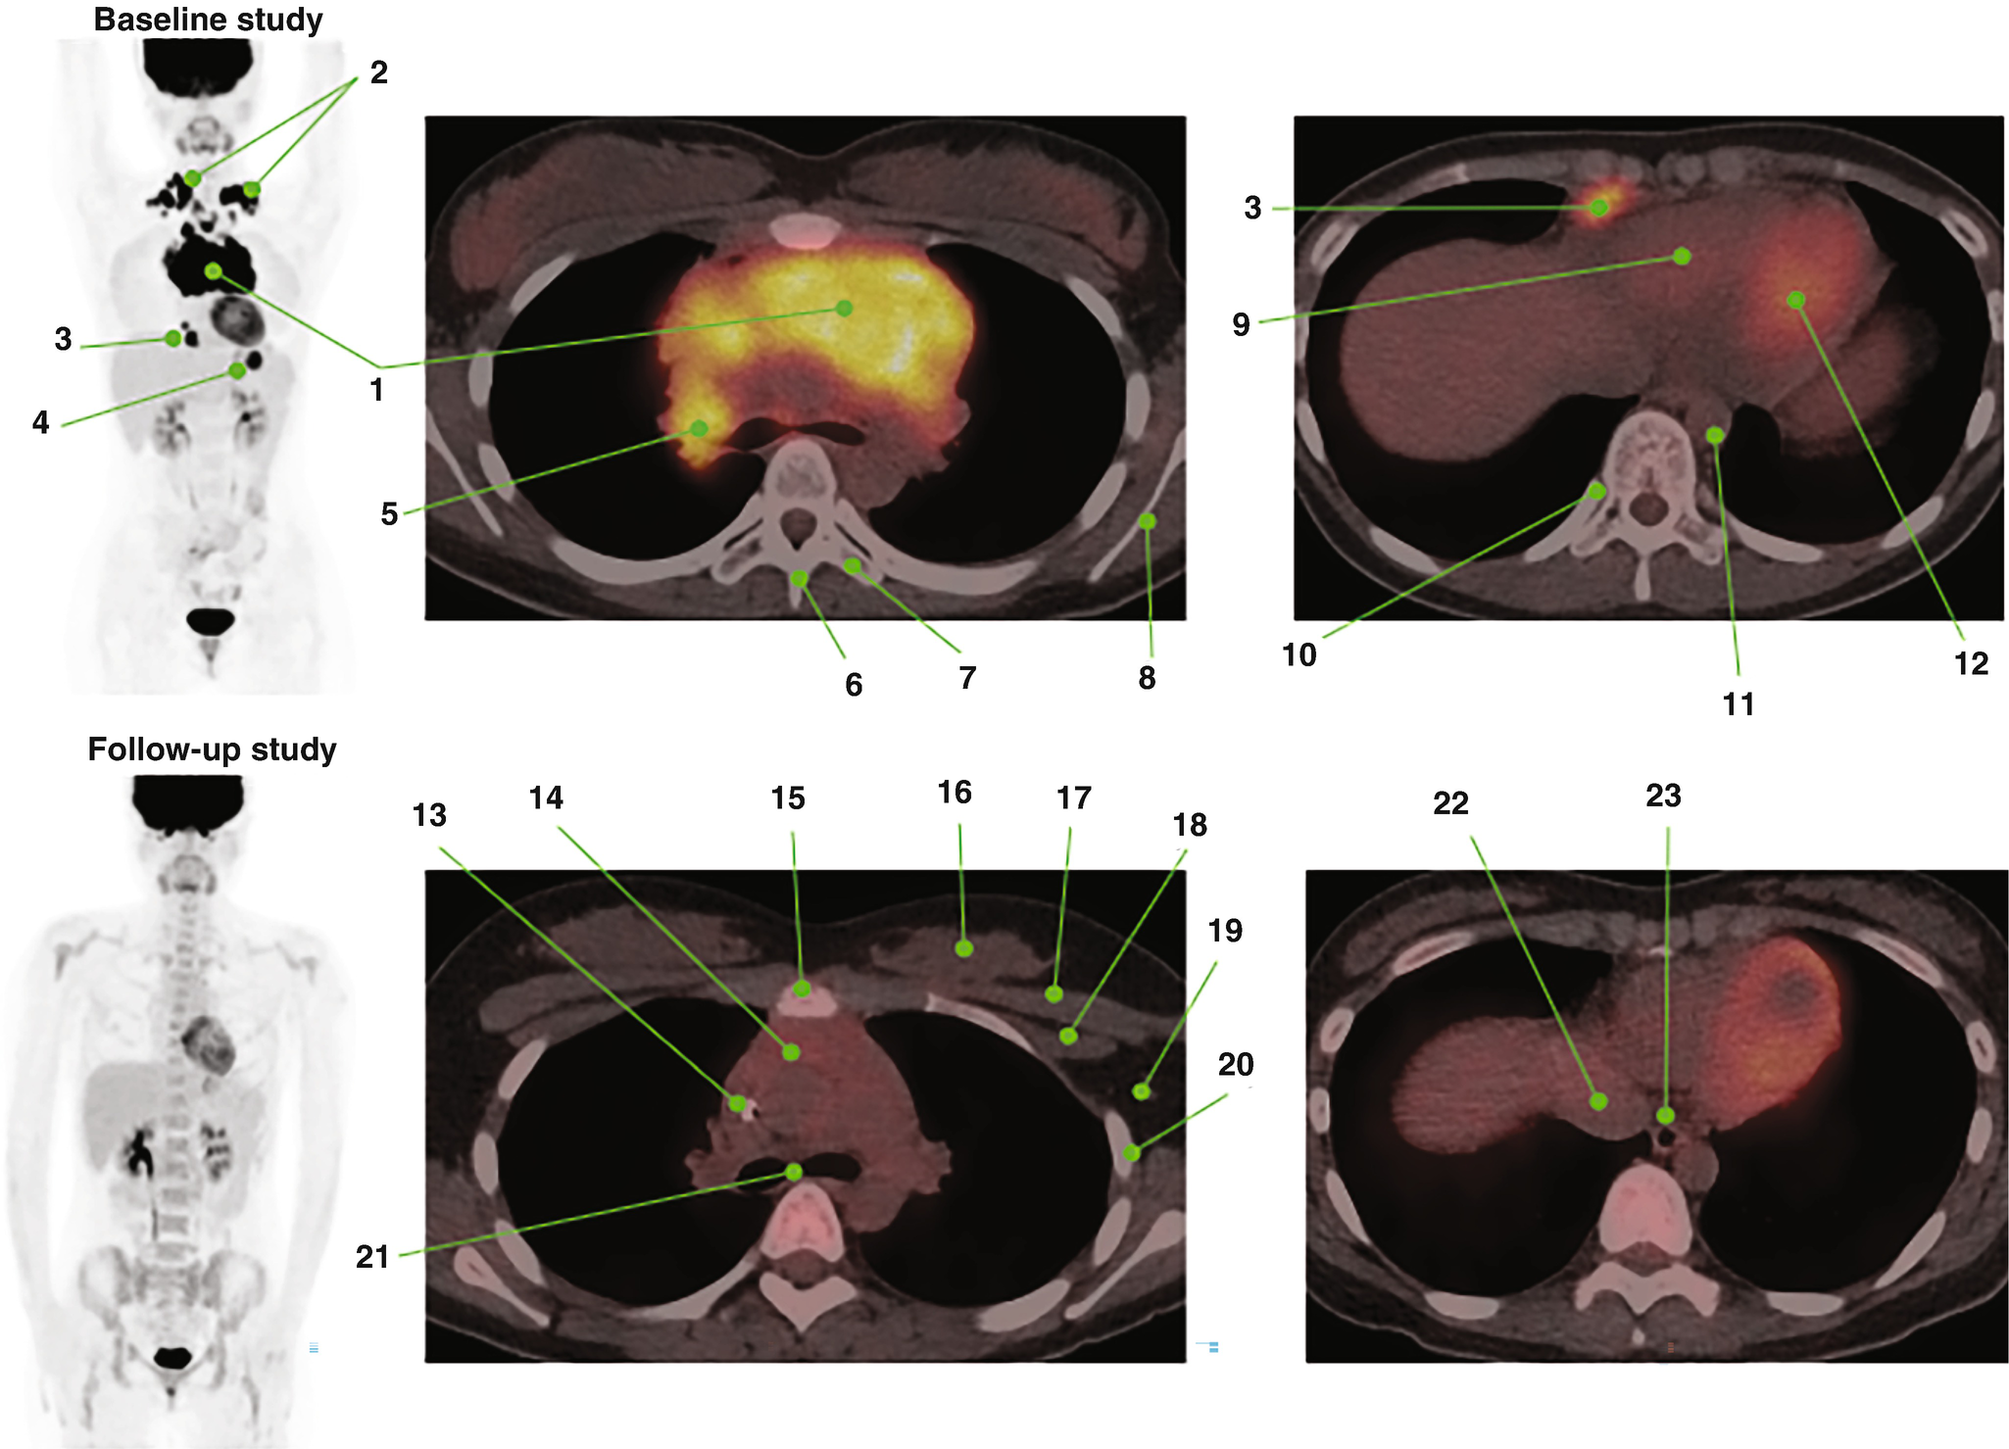

![The 4 stages of Lymphoma image by using PET/CT [17]. Focusing on ...](https://www.researchgate.net/publication/366208581/figure/fig4/AS:11431281106906315@1670896784740/The-4-stages-of-Lymphoma-image-by-using-PET-CT-17-Focusing-on-PET-MRI-scanners-since.png)